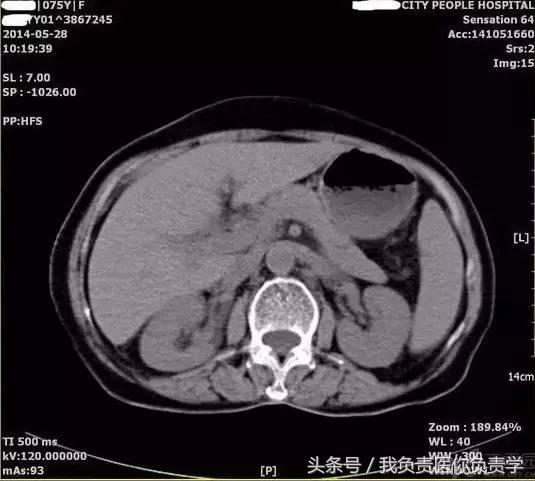

典型病例 5

患者女,75岁,右上腹疼痛就诊。查体示右上腹压痛明显,无明显腹膜炎体征。

超声检查发现胆囊内可见沉积物及结石回声,胆囊近底部可见 0.5cm 回声中断,十二指肠亦可见 0.5cm 回声中断,二者间见 5.8×4.4cm 混合性团块。

图6和7为相应CT表现

术后诊断为慢性结石性胆囊炎,胆囊-十二指肠穿孔并内瘘形成。